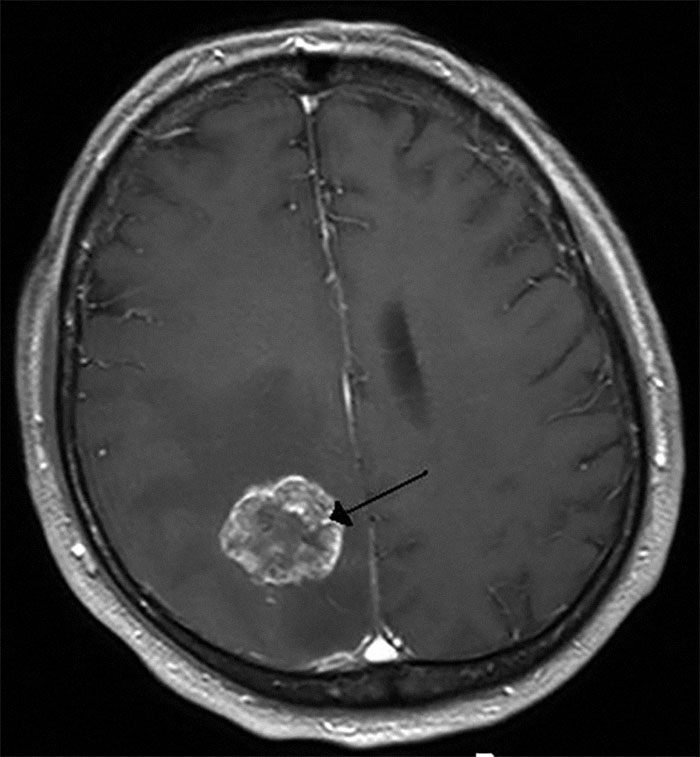

Back in 1990 was completing a group autopsy in an advanced human anatomy class. 85 year old patient had a tumor in her brain. It was the size of a Golfball on her right lobe. Unknown to her prior to death, her physician. Died in her sleep naturally. The tumor was not malignant but most likely caused some wicked headaches along with other symptoms. The stuff you find. The body is a wonder.

I actually had two strokes without knowing. I had an MRI because of a sudden weakness in my right hand and they showed up like that tumor above on my MRI. One on each side of my brain, both about the size of a quarter. The doctor said the white spots were the dead tissue in my brain. This was years ago and today I have some weakness in my left leg which my neurologist attributes to one of those strokes even though I had no recognizable symptoms at the time. And the hand weakness went away and we never found out it's cause.